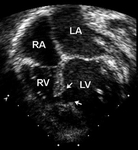

Imagen de ecocardiografía de 4 cámaras apical de una comunicación auriculoventricular (CAV) completa. Observe la comunicación interauricular (CIA) de tipo ostium primum (*) y la comunicación interventricular (CIV) de entrada contigua (flecha). (AD) aurícula derecha; (AI) aurícula izquierda; (VD) ventrículo derecho; (VI) ventrículo izquierdo

Imagen cortesía de Patrick W. O'Leary, MD